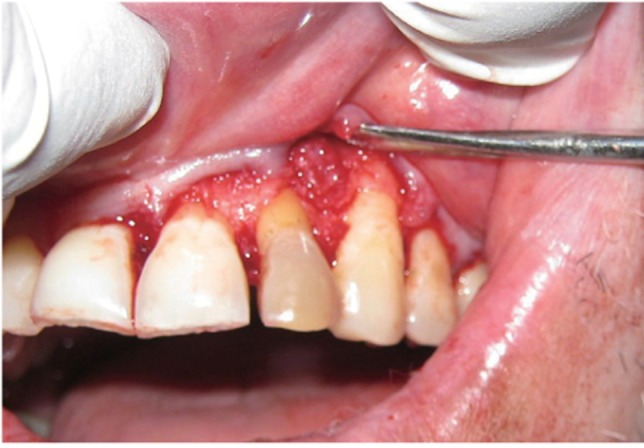

A 35 year old male patient reported to the Department of Periodontics with a complaint of pain in the upper left front tooth region associated with pus discharge for 2 months (

Figure 1). He also gave history of trauma around 7 years back and noticed discoloration of tooth with time but he took no treatment as the tooth was asymptomatic. On intraoral examination there were no carious teeth. Intraoral periapical X-ray (IOPA) was taken which revealed radiolucency along the distal side of the entire root surface to the apex (

Figure 1Preoperative view of discoloured maxillary lateral incisor.